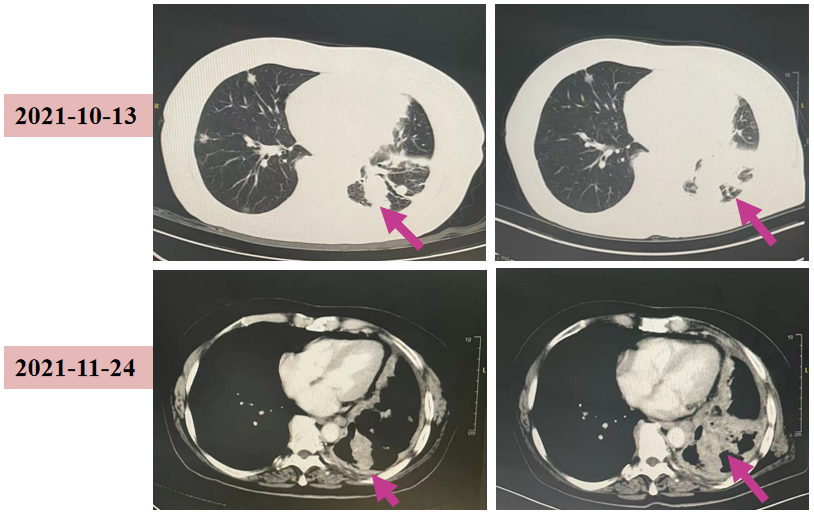

2021-10-13 我院姑息四线治疗:PE0116-I期临床研究(免疫激活类药物)。

不良事件:4级血小板下降;4级粒细胞减少;消化道出血。处理:禁食、抑酸补液、升血小板升白、免疫球蛋白、激素对症支持。转归:好转。

2021-11-24 我院胸部CT:两肺多发结节及团片影,左下肺团片较前增大;评估:PD。